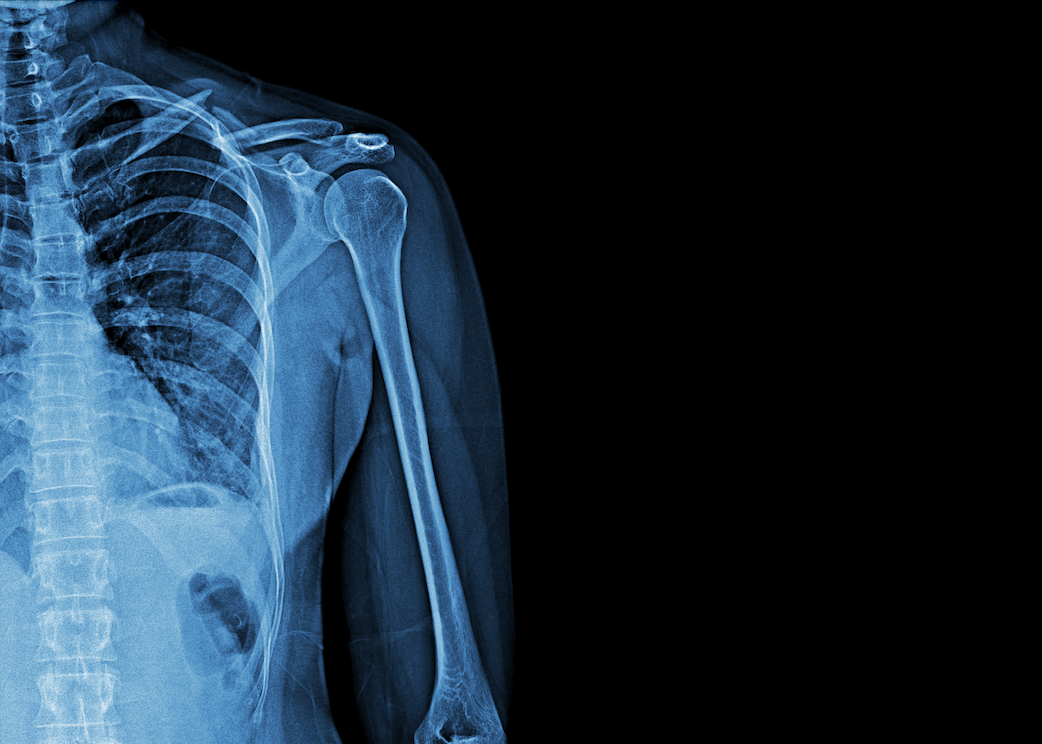

University Hospitals Plymouth NHS Trust (UHP) has launched a pilot project delivering x-rays to patients in the community.

A car with a full X-Ray kit and staffed by specialist Radiographers and Imaging Healthcare Assistants, will be out and about in Plymouth and the surrounding areas to offer support to patients who have fallen at home or in other community settings.